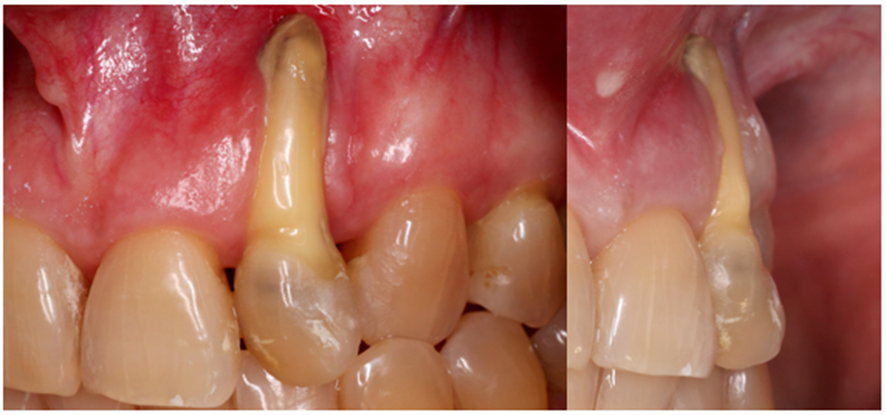

Sorrisos harmônicos e belos são cada vez mais almejados pelos pacientes que buscam tratamentos odontológicos, principalmente nos casos com patologias e/ou ausência de dentes anteriores. Além disso, vivemos em uma sociedade em que as pessoas possuem expectativas e exigências altas nos procedimentos com finalidade estética. Neste sentido, as técnicas de preservação alveolar são amplamente utilizadas em casos de manutenção do rebordo alveolar na região anterior da maxila quando se deseja instalar implantes osseointegráveis. Esta abordagem justifica-se pelo fato da reabsorção óssea ocorrer naturalmente após a perda dos elementos dentários. Nos casos em que a perda óssea vestibular é muito extensa e o tecido gengival é insuficiente, não há a possibilidade de preservar o volume ósseo imediatamente após a exodontia (Figuras 1 e 2).

Sendo assim, na dependência do nível de destruição dos tecidos de suporte/proteção dental, a presença de defeitos de tecido duro e/ou mole podem dificultar o restabelecimento da estética e da função mastigatória, ou até mesmo impedir a realização de reabilitação implantossuportada.

Nossa proposta é relatar o caso clínico da paciente M. S., que procurou a clínica do Curso de Especialização de Implantodontia da Universidade Paulista (Grupo Apoio) devido à condição do dente 22. Uma vez que a destruição periodontal era muito extensa, incluindo o ápice dental, foi indicada a exodontia do dente 22. Buscando reduzir o número de procedimentos cirúrgicos e o tempo necessário para a finalização do caso, foi realizada a reconstrução óssea imediatamente após a remoção do dente. Foi realizada a técnica de Regeneração Óssea Guiada (ROG) com membrana não absorvível de PTFE denso (Cytoplast), associada a enxerto ósseo xenógeno composto por 75% de hidroxiapatita e 25% de colágeno do tipo I (Extra Graft) (Vídeo 1 e Figura 3).